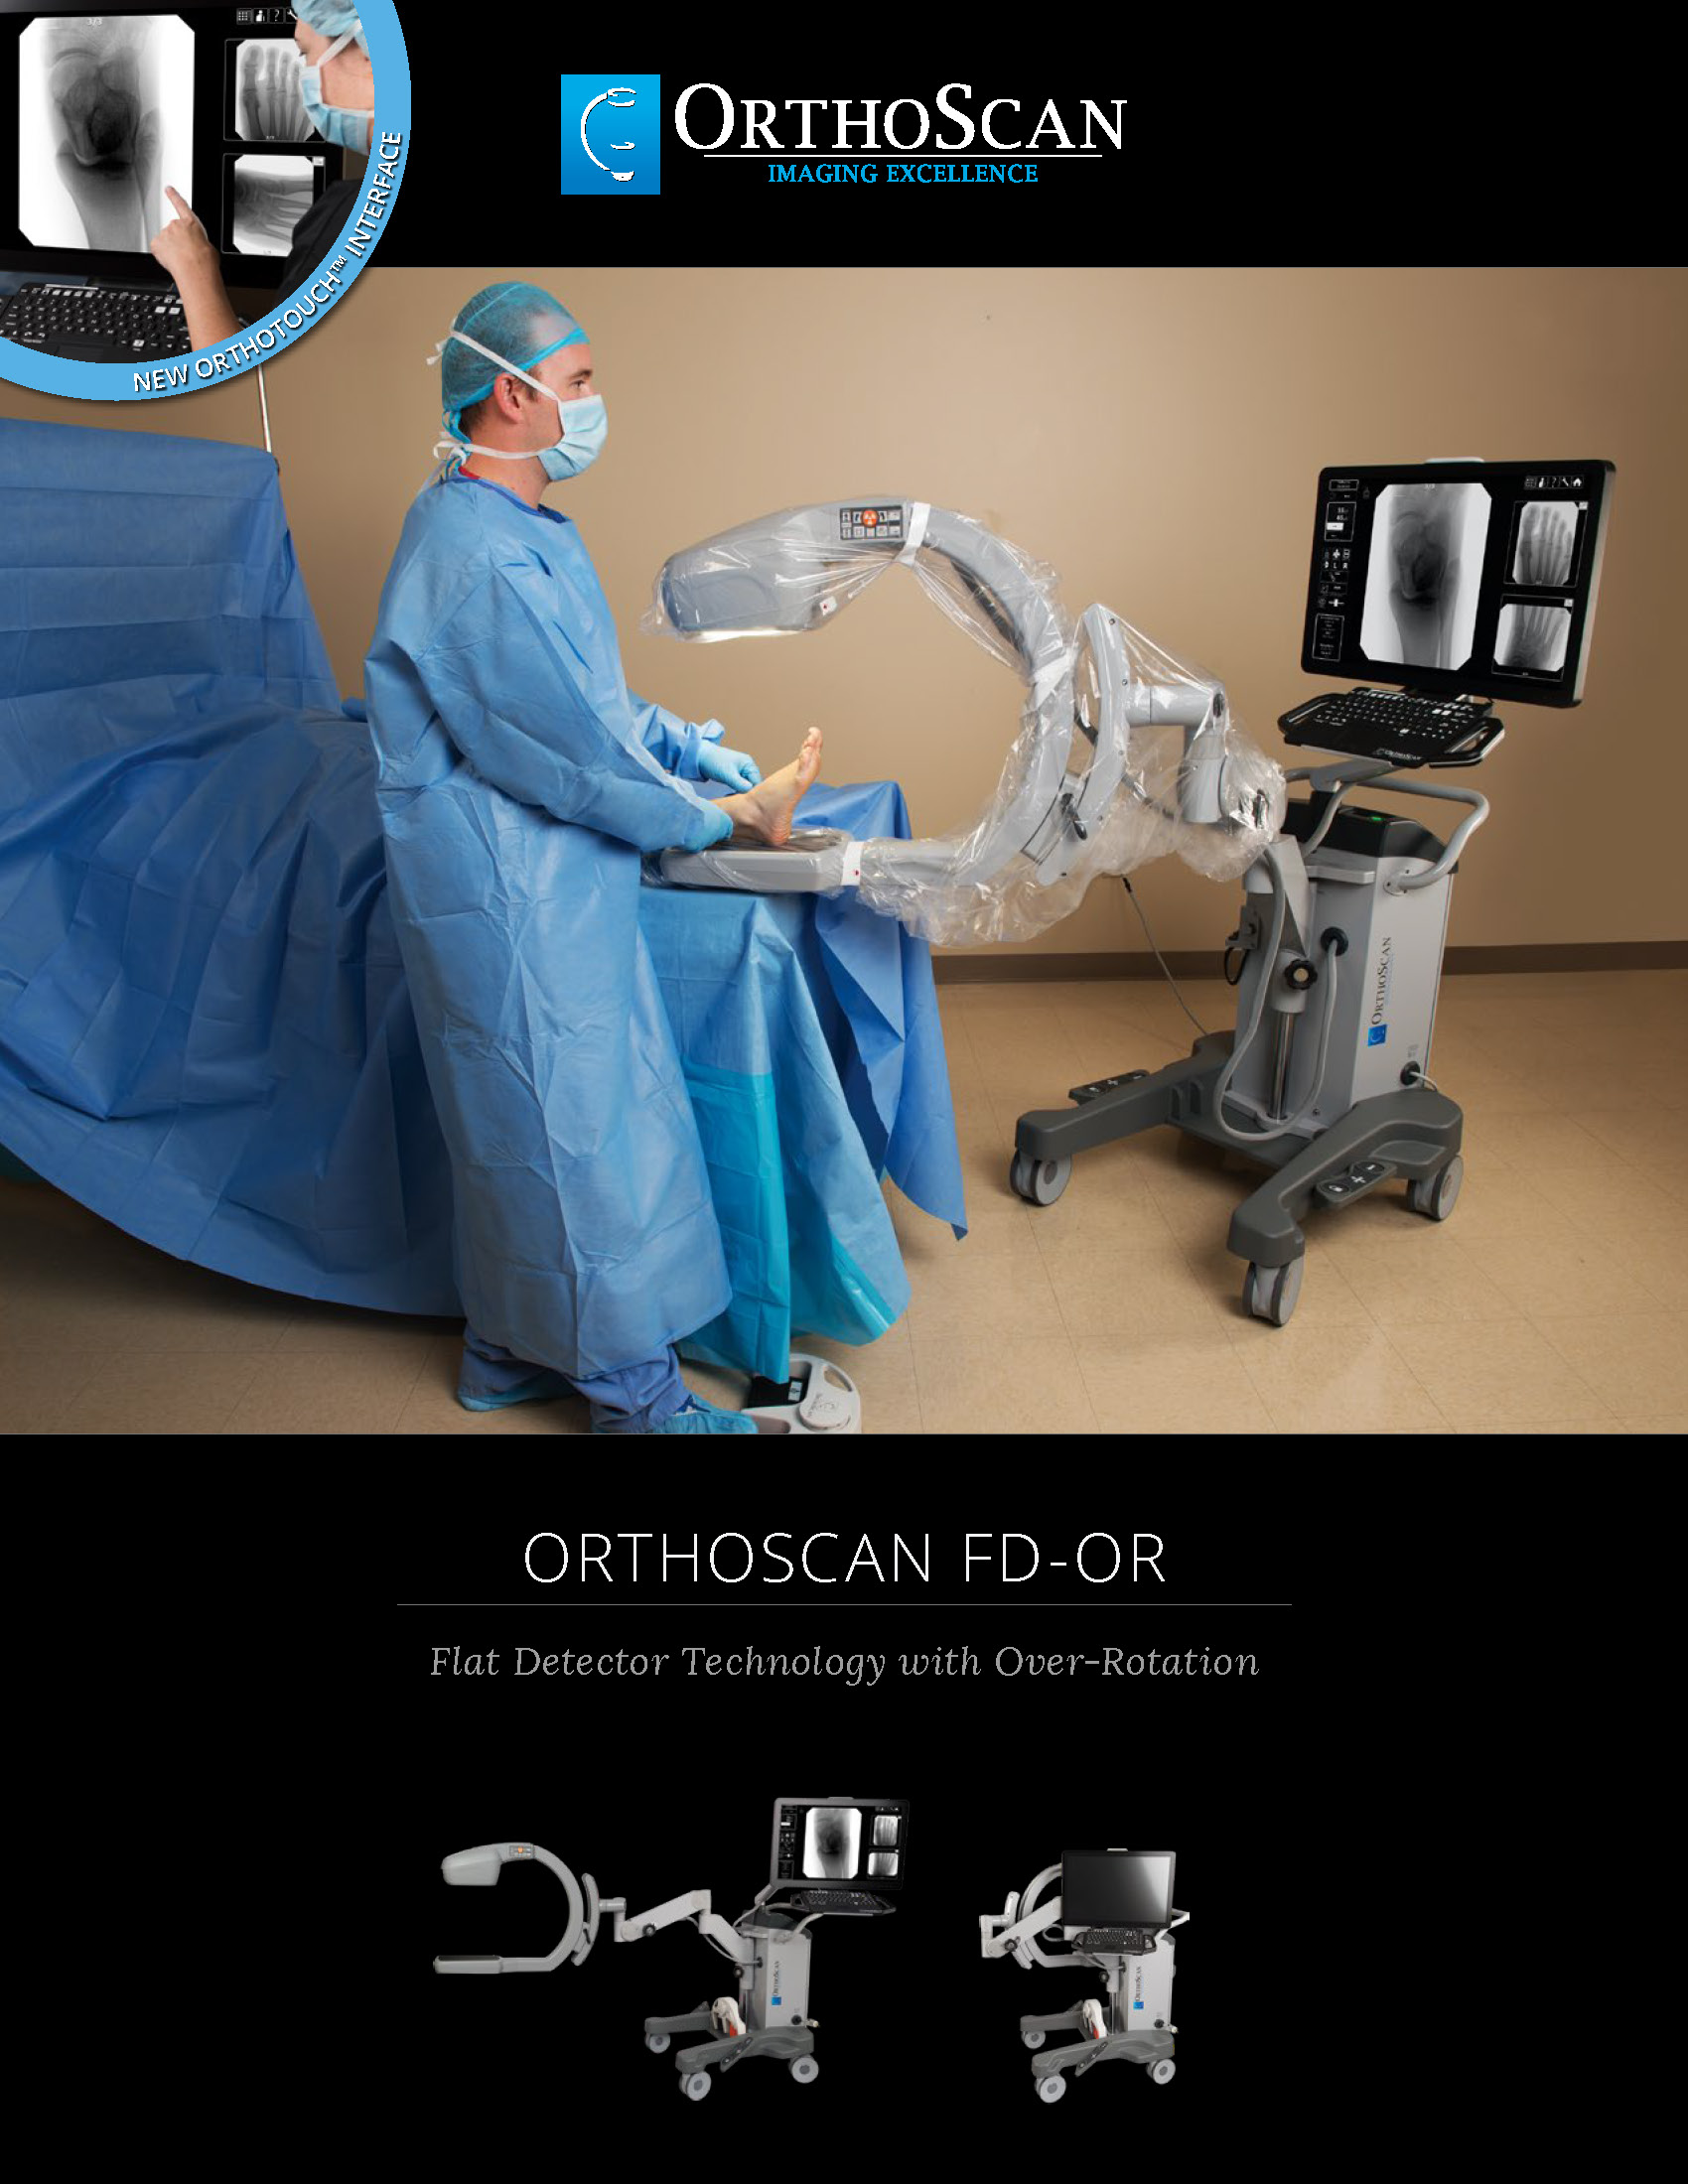

The Advanced Arthritis Relief Program (AARP) is a knee osteoarthritis (OA) treatment system that consists of fluoroscopic guided injections of Hyaluronic Acid, targeted Physical Therapy, and a special uploading Knee Brace. It’s MD, MP, and PA approved and covered by all major insurance carriers as well as Medicare.

2019 Fee Schedule & Coding Determination changes Osteoarthritis Joint Treatment & Pain Relief. After Standard of care for knee OA, MEDICARE requires patients try and fail viscosupplementation therapy prior to approving total knee arthroplasty (TKA). The AARP is this type of therapy that is approved by Medicare. It combines viscosupplementation with physical therapy and a specialized knee bracing procedure that has been delivering near perfect results.

2019 Fee Schedule & Coding Determination changes Osteoarthritis Joint Treatment & Pain Relief. After Standard of care for knee OA, MEDICARE requires patients try and fail viscosupplementation therapy prior to approving total knee arthroplasty (TKA). The AARP is this type of therapy that is approved by Medicare. It combines viscosupplementation with physical therapy and a specialized knee bracing procedure that has been delivering near perfect results.